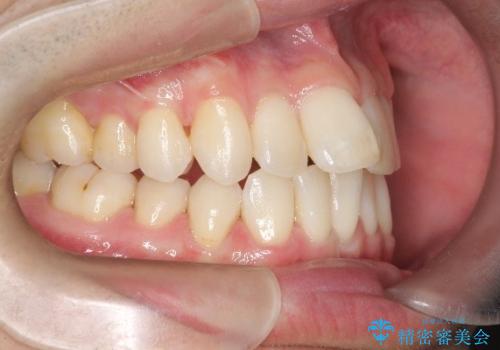

前歯の重なりとガタガタをマウスピースで改善した症例

初診時の歯並びの状態としては、上下ともに前歯部の中等度のがたつきがあり、上の前歯が重なっている状態でした。

また元々下の前歯は1本少なく、歯の本数が少ないことを前提とした矯正治療を行いました。

抜歯は必要なく、マウスピース矯正にて治療を行っています。

見た目、嚙み合わせ及び、治療期間や施術内容に大変ご満足いただきました。